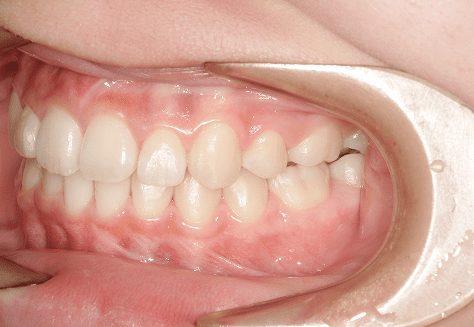

M.H

治療前

治療後

主訴

前歯が出ている。下の歯並びが特に気になる。奥歯でしっかり噛めない。

診断

上顎前突・叢生・シザーズバイト

年齢/性別

20代/男性

抜歯部位

下顎両側大三大臼歯(口腔外科にて)

上顎両側第一小臼歯・下顎左側側切歯

(当院にて5,500円×3) -

使用装置

上下エッジワイズ→インビザライン(PBM使用)

保定装置

上下ビベラリテーナー

料金

初回資料採得・・・・・・・30,000円

診断料・・・・・・・・・・33,000円

動的治療終了時資料採得・・5,500円 -

基本料金

880,000円

診察料金

5,500円×44回

治療期間

3年6カ月